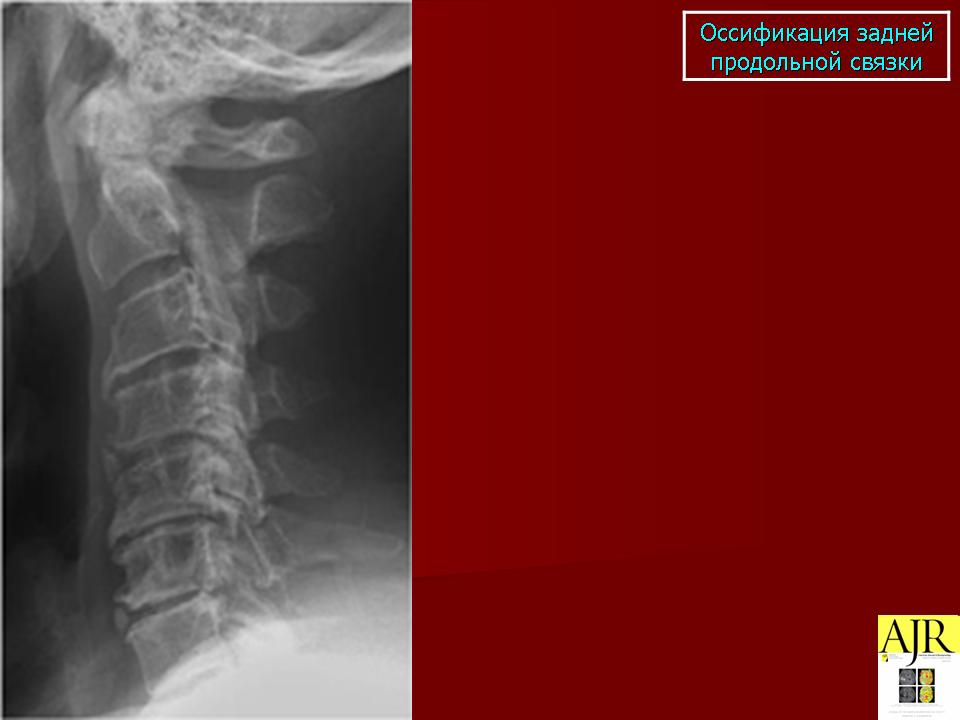

КСС. Оссификации. +

Оссификации.